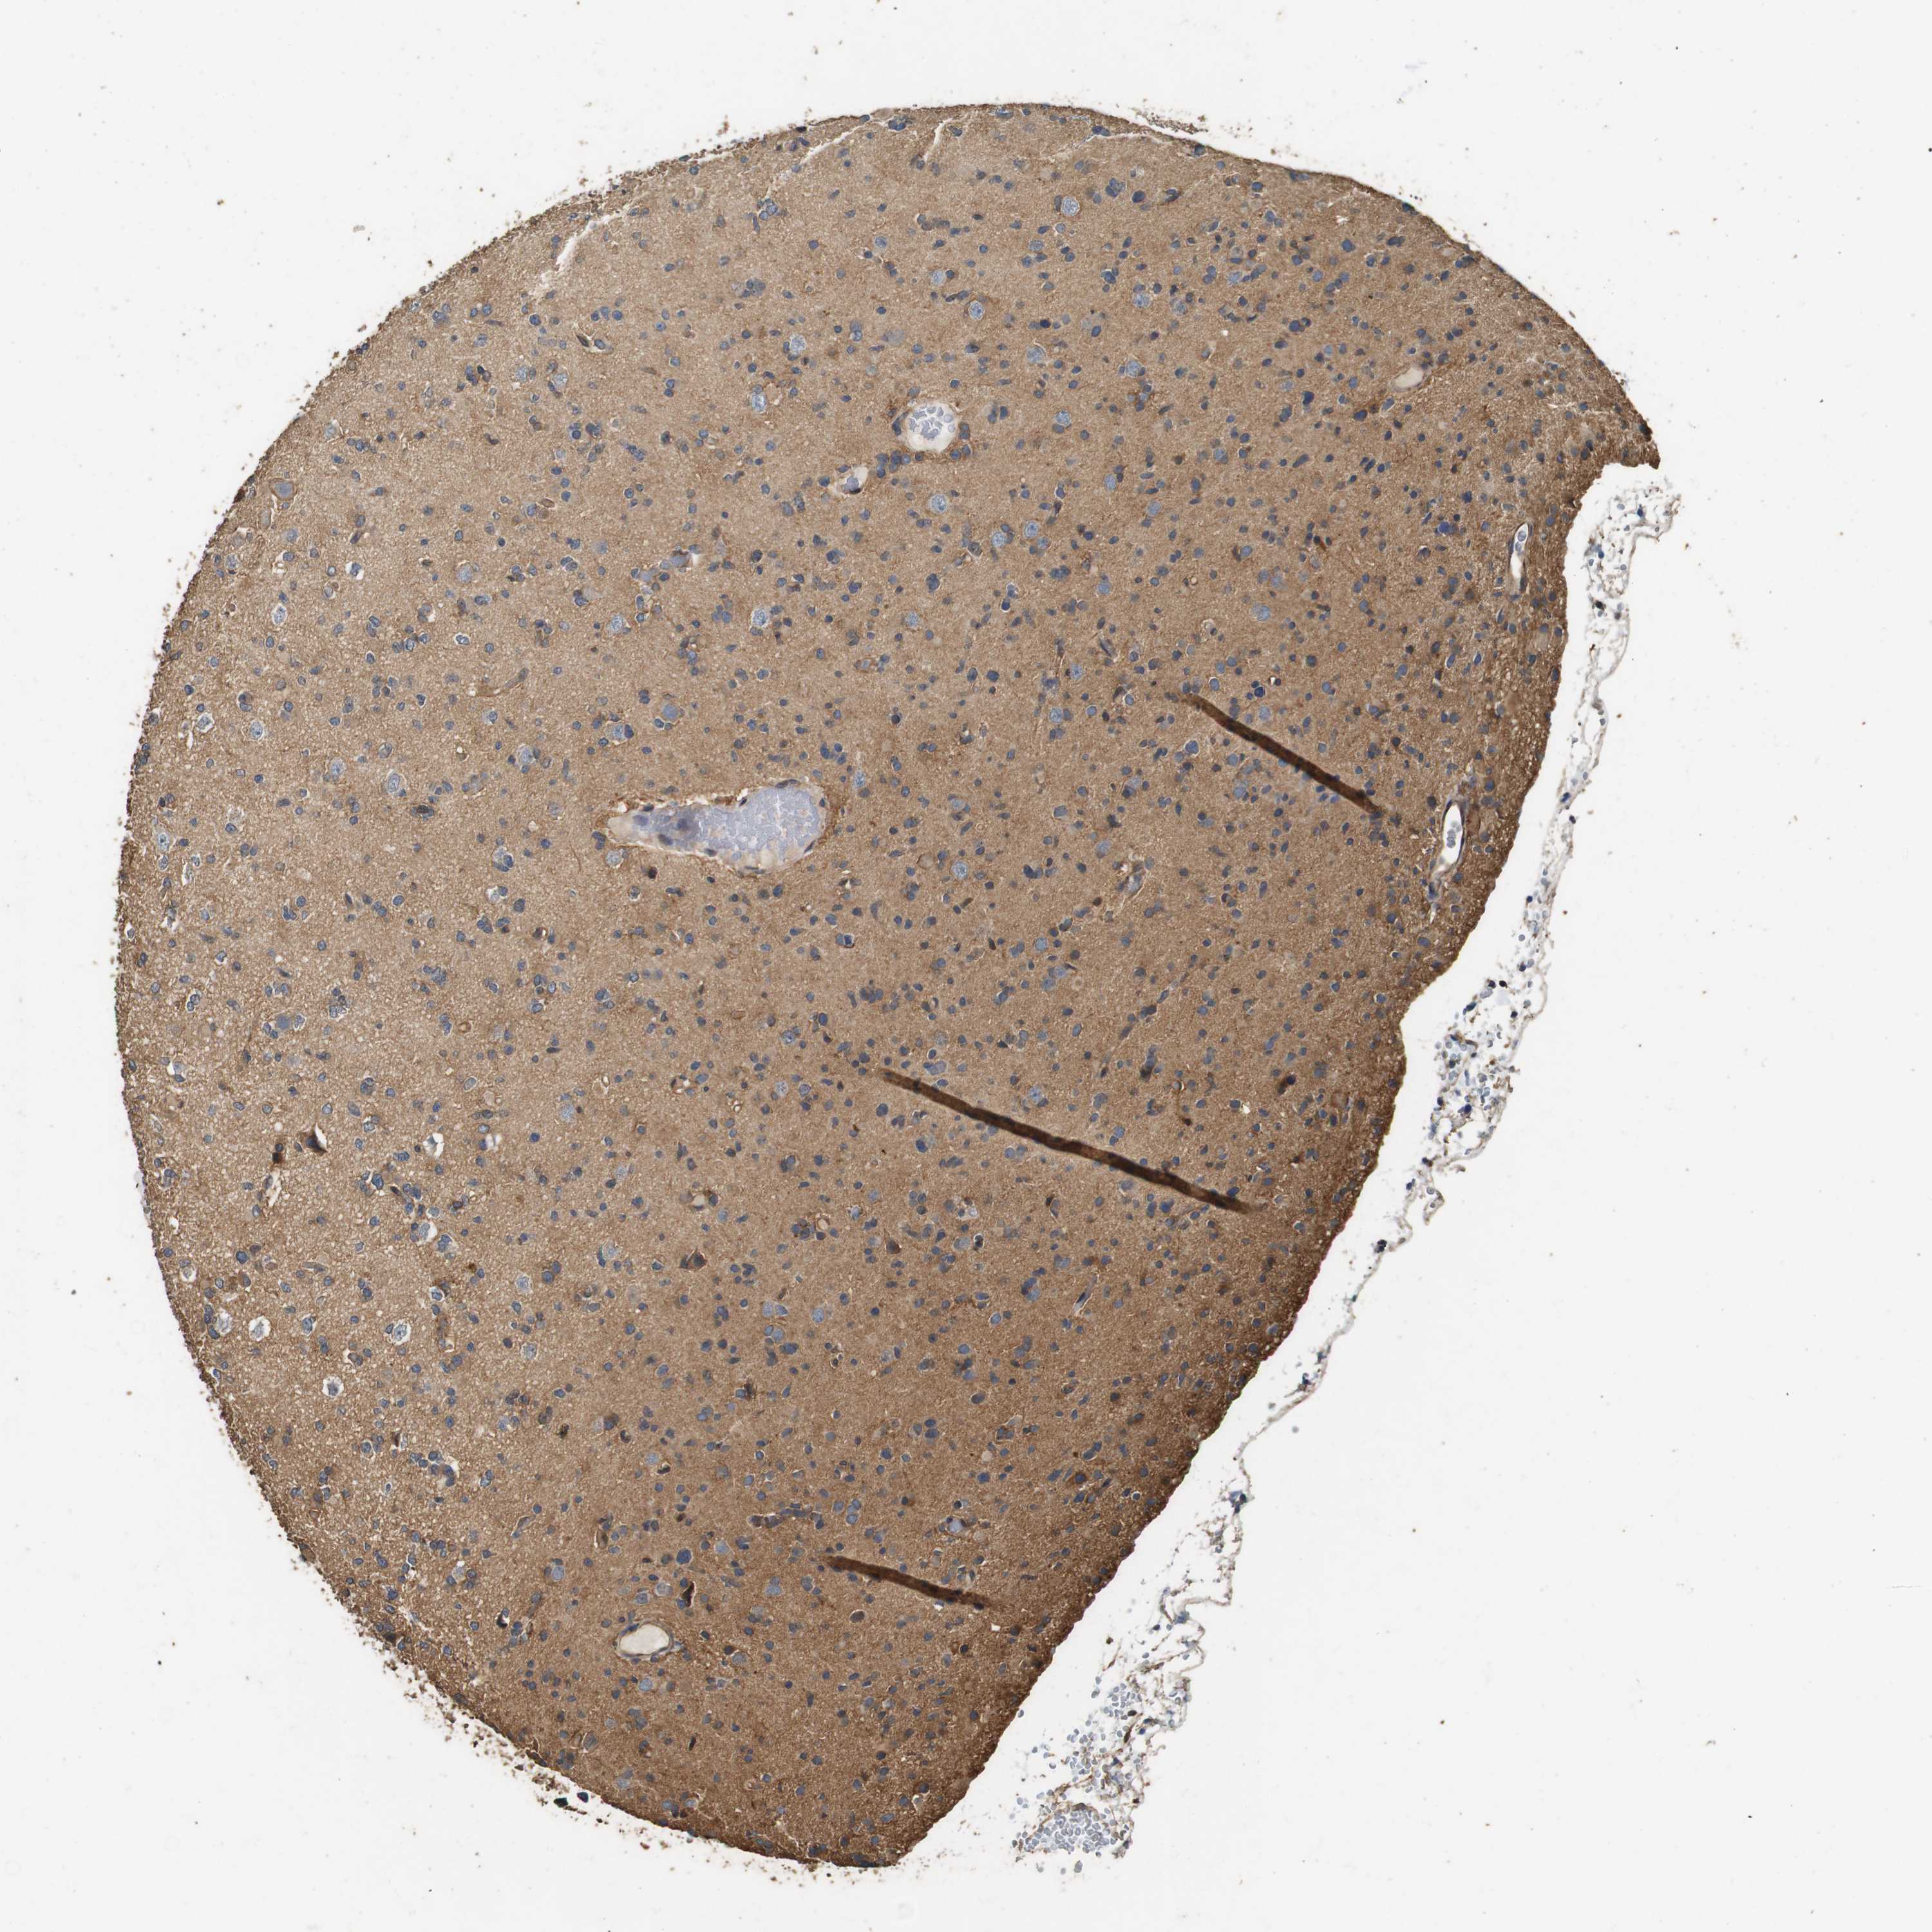

GLIOMA - Protein expressioni

A mouse-over function shows sample information and annotation data. Click on an image to view it in a full screen mode. Samples can be filtered based on level of antibody staining by selecting one or several of the following categories: high, medium, low and not detected. The assay and annotation is described here.

Note that samples used for immunohistochemistry by the Human Protein Atlas do not correspond to samples in the TCGA dataset.

Antibody stainingi

Antibody staining in the annotated cell types in the current human tissue is reported as not detected, low, medium, or high, based on conventional immunohistochemistry profiling in selected tissues. This score is based on the combination of the staining intensity and fraction of stained cells.

Each image is clickable and will lead to virtual microscopy that enables deeper exploration of all samples and also displays staining intensity scores, fraction scores and subcellular localization as well as patient and tissue information for each sample.

Antibody HPA014166

Antibody HPA025240

Staining

High

Medium

Low

Not detected

Intensity

Strong

Moderate

Weak

Negative

Quantity

>75%

75%-25%

<25%

None

Location

Nuclear

Cytoplasmic/membranous

Cytoplasmic/membranous,nuclear

Glioma, malignant, High grade

Glioma, malignant, Low grade